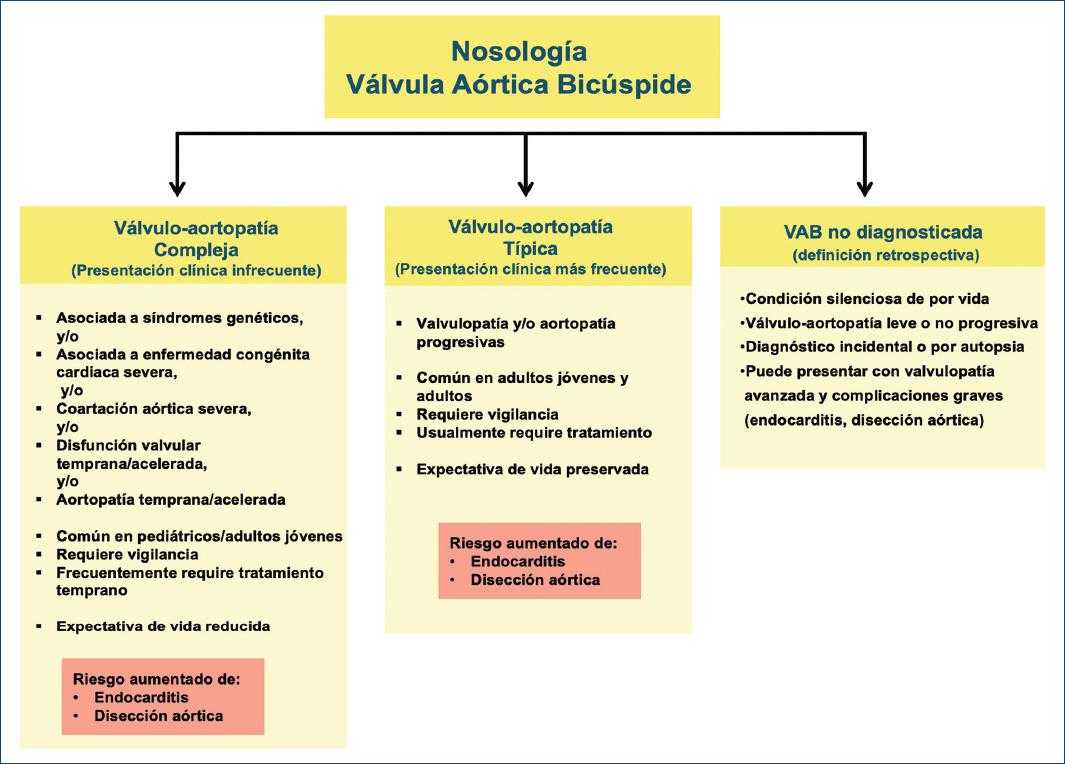

La condición congénita de válvula aórtica bicúspide (VAB) es una válvulo-aortopatía caracterizada por heterogeneidad significativa de sus expresiones fenotípicas valvulares y aórticas, de sus trastornos asociados, de sus complicaciones y de su pronóstico2-6. Para conciliar esta heterogeneidad clínica y pronóstica, la condición de la VAB se clasifica ampliamente en tres subgrupos clínico-pronósticos (Fig. 1):

- La válvulo-aortopatía compleja1,5,6 se caracteriza por trastornos concomitantes o asociados que pueden ser clínica y pronósticamente peores que la VAB per se (p. ej., síndrome de Turner, síndrome de Loeys-Dietz, coartación aórtica severa y complejo de Shone) y/o por disfunción valvular y/o aortopatía tempranas/aceleradas, más comúnmente diagnosticada en la población pediátrica, adolescente y adulta joven7,8. Esta presentación con frecuencia requiere de tratamiento quirúrgico/invasivo temprano y una estrecha vigilancia.

- La válvulo-aortopatía típica1,2,6 es el tipo más común, con disfunción progresiva de la VAB y/o dilatación aórtica sin otros trastornos asociados severos, se diagnostica con mayor frecuencia en adultos jóvenes y adultos, requiere vigilancia a largo plazo y comúnmente requiere tratamiento quirúrgico/invasivo eventualmente. Los pacientes con válvulo-aortopatías de presentación compleja y de presentación típica están en riesgo de desarrollar endocarditis infecciosa y disección aórtica (Fig. 1), aunque la disección aórtica es extremadamente rara en niños con VAB y rara en adultos sin dilatación aórtica2,9.

- El subgrupo de la VAB no diagnosticada o sin complicaciones2 constituye una condición silenciosa de por vida con válvulo-aortopatía leve o no progresiva que no se manifiesta clínicamente, pero puede salir a la luz en la autopsia o incidentalmente por imágenes (Fig. 1); por lo tanto, representa una definición retrospectiva. Sin embargo, la VAB no diagnosticada puede iniciar en algunos casos con valvulopatía avanzada o complicaciones graves (endocarditis infecciosa o disección aórtica). Una diferencia crítica entre las válvulo-aortopatías típicas y complejas es la sobrevida general a largo plazo preservada y similar a la de la población general en pacientes con la válvulo-aortopatía típica10, mientras que la sobrevida del paciente con válvulo-aortopatía compleja puede estar comprometida1.

Figura 1 Nosología de la afección congénita de la válvula aórtica bicúspide. Izquierda: las presentaciones anatómica y pronósticamente complejas de la válvulo-aortopatía bicúspide (VAB) son aquellas asociadas con síndromes, obstrucciones del lado izquierdo, coartación aórtica severa, disfunción valvular temprana/acelerada (estenosis o insuficiencia) y/o aortopatía temprana, manifestada como dilatación de la aorta torácica. Estas afecciones se diagnostican con mayor frecuencia en la infancia, la adolescencia y la edad adulta joven. Medio: la válvulo-aortopatía anatómica y pronósticamente típica generalmente se diagnostica en adultos jóvenes y de mediana edad, aunque también puede diagnosticarse en niños y comprende varios grados de disfunción valvular progresiva con una alta incidencia acumulativa de válvulo-aortopatía a largo plazo, manifestada como dilatación aórtica torácica, sin condiciones asociadas severas. Las formas de presentación compleja y típica son susceptibles al desarrollo de endocarditis infecciosa y disección aórtica, aunque la disección es rara en la población pediátrica y en adultos sin dilatación aórtica. Derecha: la forma no diagnosticada o no complicada no se diagnostica en la vida del paciente o se diagnostica durante la vida del paciente, pero no causa complicaciones que requieran tratamiento, aunque nuevos datos sugieren que el paciente con VAB no diagnosticada puede iniciar con complicaciones severas como disección aortica y endocarditis (modificada de Michelena et al., 20206 con permiso de Elsevier).